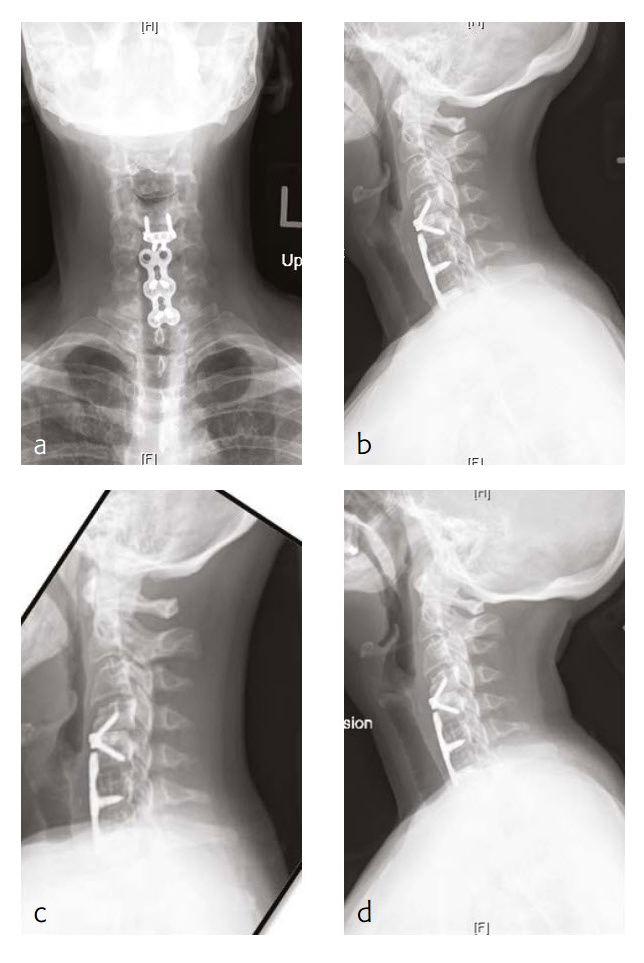

Follow-up (4 months)

At the patient follow-up at 4 months postoperative, he described complete resolution of left upper extremity pain (Fig 2). He was also happy with his left upper extremity strength and was extremely pleased with his progress. He continued to have no left upper extremity pain. He also believed that he had made significant progress in terms of his left upper extremity range-of-motion and strength.